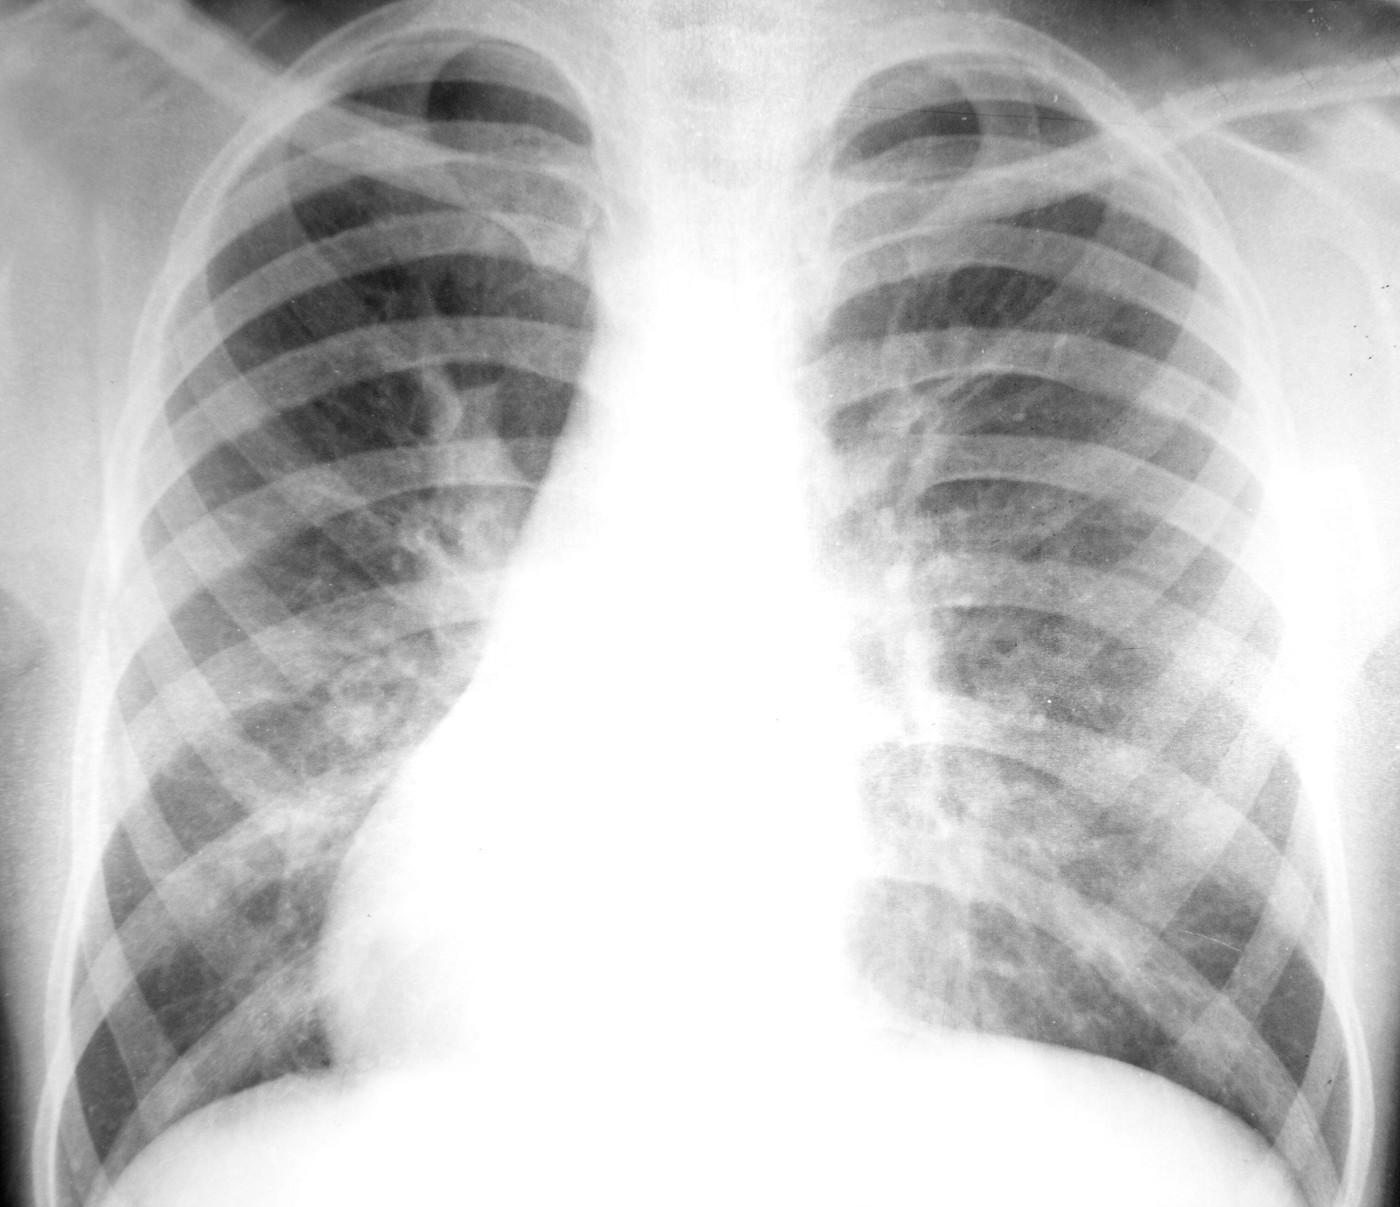

Descoperă care sunt simptomele cancerului de plămâni și când trebuie neapărat să mergi la medic Cancerul pulmonar, un inamic tăcut. Simptomele ce arată că ești bolnav. Poți face boala dacă nu ai fumat? Află răspunsul Cancerul pulmonar, un inamic tăcut. Simptomele ce arată că ești bolnav. Poți face boala dacă nu ai fumat? Află răspunsul Cancerul pulmonar, un inamic tăcut. Simptomele ce arată că ești bolnav. Poți face boala dacă nu ai fumat? Află răspunsul Cancerul pulmonar, un inamic tăcut. Simptomele ce arată că ești bolnav. Poți face boala dacă nu ai fumat? Află răspunsul